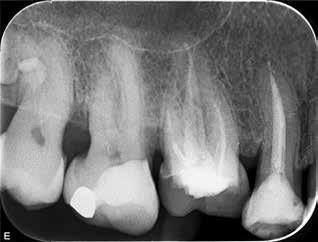

Knækket rodfil

i distal kanal -6

PATIENTTILFÆLDE

Patienten henvender sig på klinikken pga. akutte smerter fra -6. Der laves akut oplukning og findes tre kanaler. Ved udrensning i distale kanal for at finde endeligt rodmål knækker ca. 1-2 mm af fil 08 i kanalen. Patienten bliver informeret og henvist til specialtandlæge for videre behandling.

LÆRING

Det fremgår, at der er tale om en filstørrelse 08, altså den tyndeste fil, der findes. Ved flerrodede tænder med lange, krumme og/eller oblitererede (“tilgroede”) rodkanaler er risikoen for filfraktur højere.

Det anbefales derfor, at du anvender meget fleksible file, skyller kanalerne hyppigt undervejs og kasserer file, der udviser svaghedstegn (fx vrid eller buk på filens arbejdende del). Du bør desuden kassere de mindste file efter brug, da risiko for usynlige svagheder i disse er høj. Alternativt kan du henvise til en tandlæge med særlig kompetence inden for rodbehandling, hvis du vurderer, at en rodbehandling er særligt vanskelig.

Se også guiden "Sådan fjerner du et filfragment" på side 774.